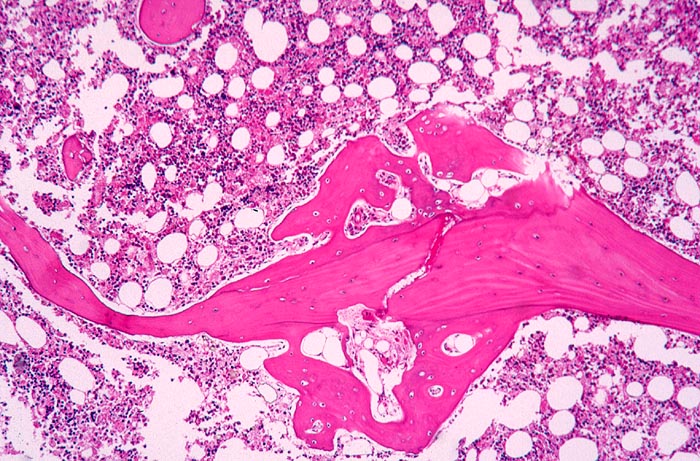

• Linker Wirbelkörper mit Osteoporose, rechts ein normaler Wirbelkörper zum Vergleich.

• Deutliche Rarefizierung und Atrophie vor allem der horizontalen Spongiosabälkchen.

• Hochgradige Reduktion der intertrabekulären Vernetzung.

• Reaktiv hyperplastisches blutbildendes Mark.